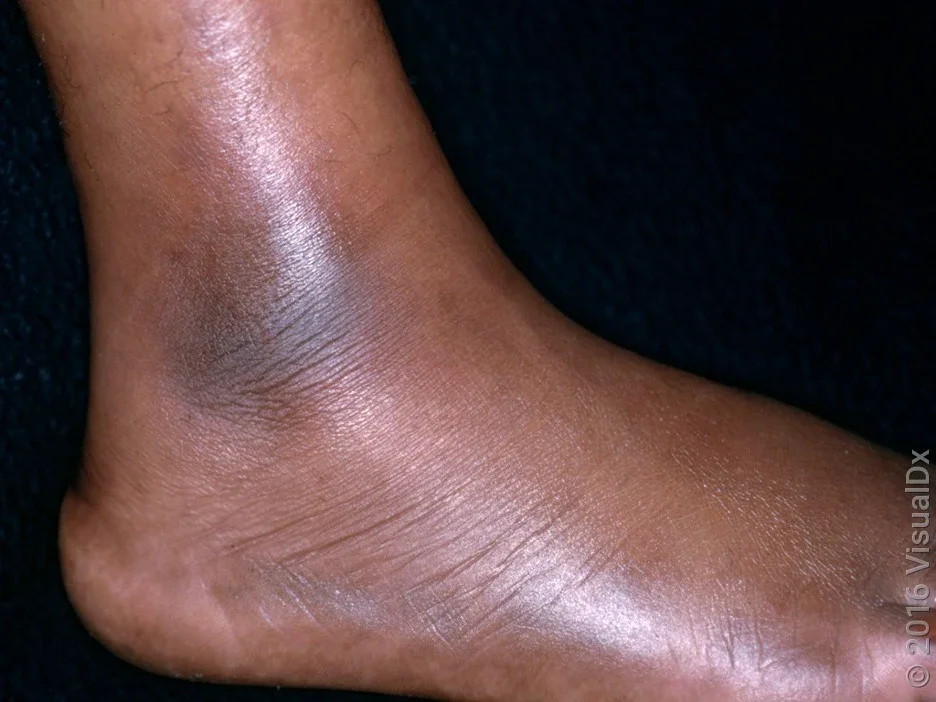

Erythema nodosum causes tender, warm, reddish-purple lumps about 1 inch to 2 inches wide. In people with darker skin tones, the skin might appear darker in the tender spot, or there may be no color change at all.

EN lumps are smooth — they don’t open up or ooze. They usually occur on the shins, but other areas may be involved, including the forearms, legs, and buttocks.

EN takes a couple of days to pop up, and the lumps go away within 2 months. As they heal, the color changes from red-purple to yellow-brown-blue-green (like a bruise). Sometimes, skin darkening can continue for months after EN heals.

Pictures of erythema nodosum

Here are some pictures of erythema nodosum on different skin tones.